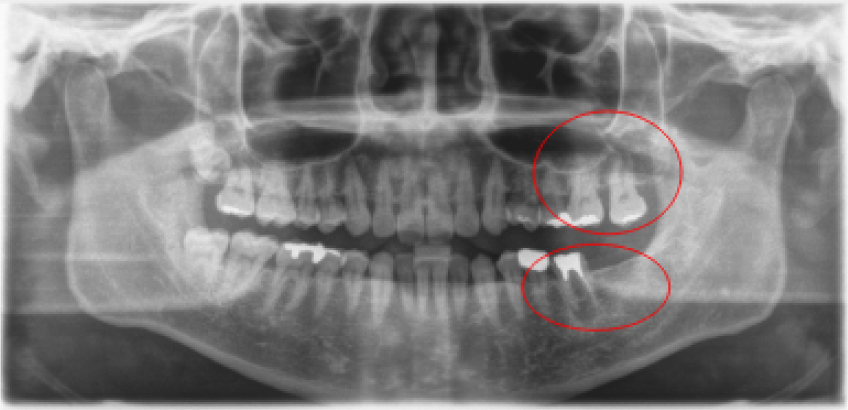

治療前治療後

| 治療内容 | インプラント奥歯1本 |

|---|---|

| 患者様の年齢 | 48歳 |

| 患者様の性別 | 男性 |

| 治療期間 | 5ヶ月 |

| 治療回数 | 25回程度 |

| 治療費用 | 50万円 |

| 治療で得られるメリット |

|

| 治療する際に起こる リスク・副作用 |